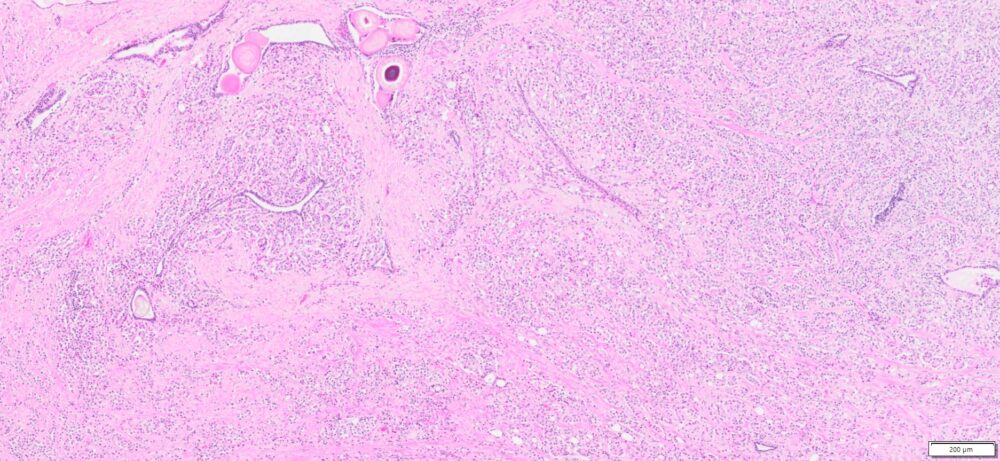

| Tissue | Pathology Diagnosis | Gender/ Age (year) | %Tumor Area | Tumor Grade | TMN/Stage | IHC data |

| Prostate | Human Prostate Adenocarcinoma, Acinar type, Gleason score 9 (4+5) | Male/73 | 50% | II | pT3b, PN1 Mx | NA |